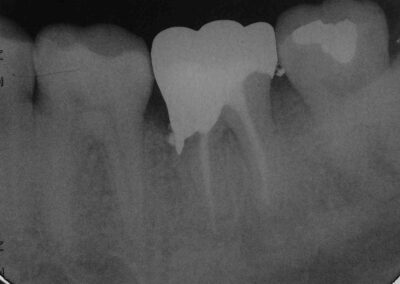

Eine solche ist allerdings nicht immer erforderlich, wie man an diesem Beispiel eines 37 sieht, der im Bereich des mesiovestibulären Höckers im Mai 2008 nur wenige Wochen nach der WF ausgesprochen tief frakturierte. Dass man in einem solchen Fall – um dem Patienten die chirurgische Kronenverlängerung zu ersparen – in weiten Bereichen „blind“, also nach Gefühl präparieren muss, versteht sich von selbst. Kautern lässt sich, nachdem man eine kleine Rille in den Knochen präpariert hat, um den Zahn nichtdestotrotz in allen Bereichen von der Krone fassen zu lassen, zur Blutstillung vor der Abformung nicht vermeiden. Natürlich kann man hier keine Hohlkehlpräparation mehr durchführen. Wenn die (hochgoldhaltigen) Kronenränder allerdings rasierklingenscharf auslaufen, werden sie in aller Regel wunderbar toleriert.